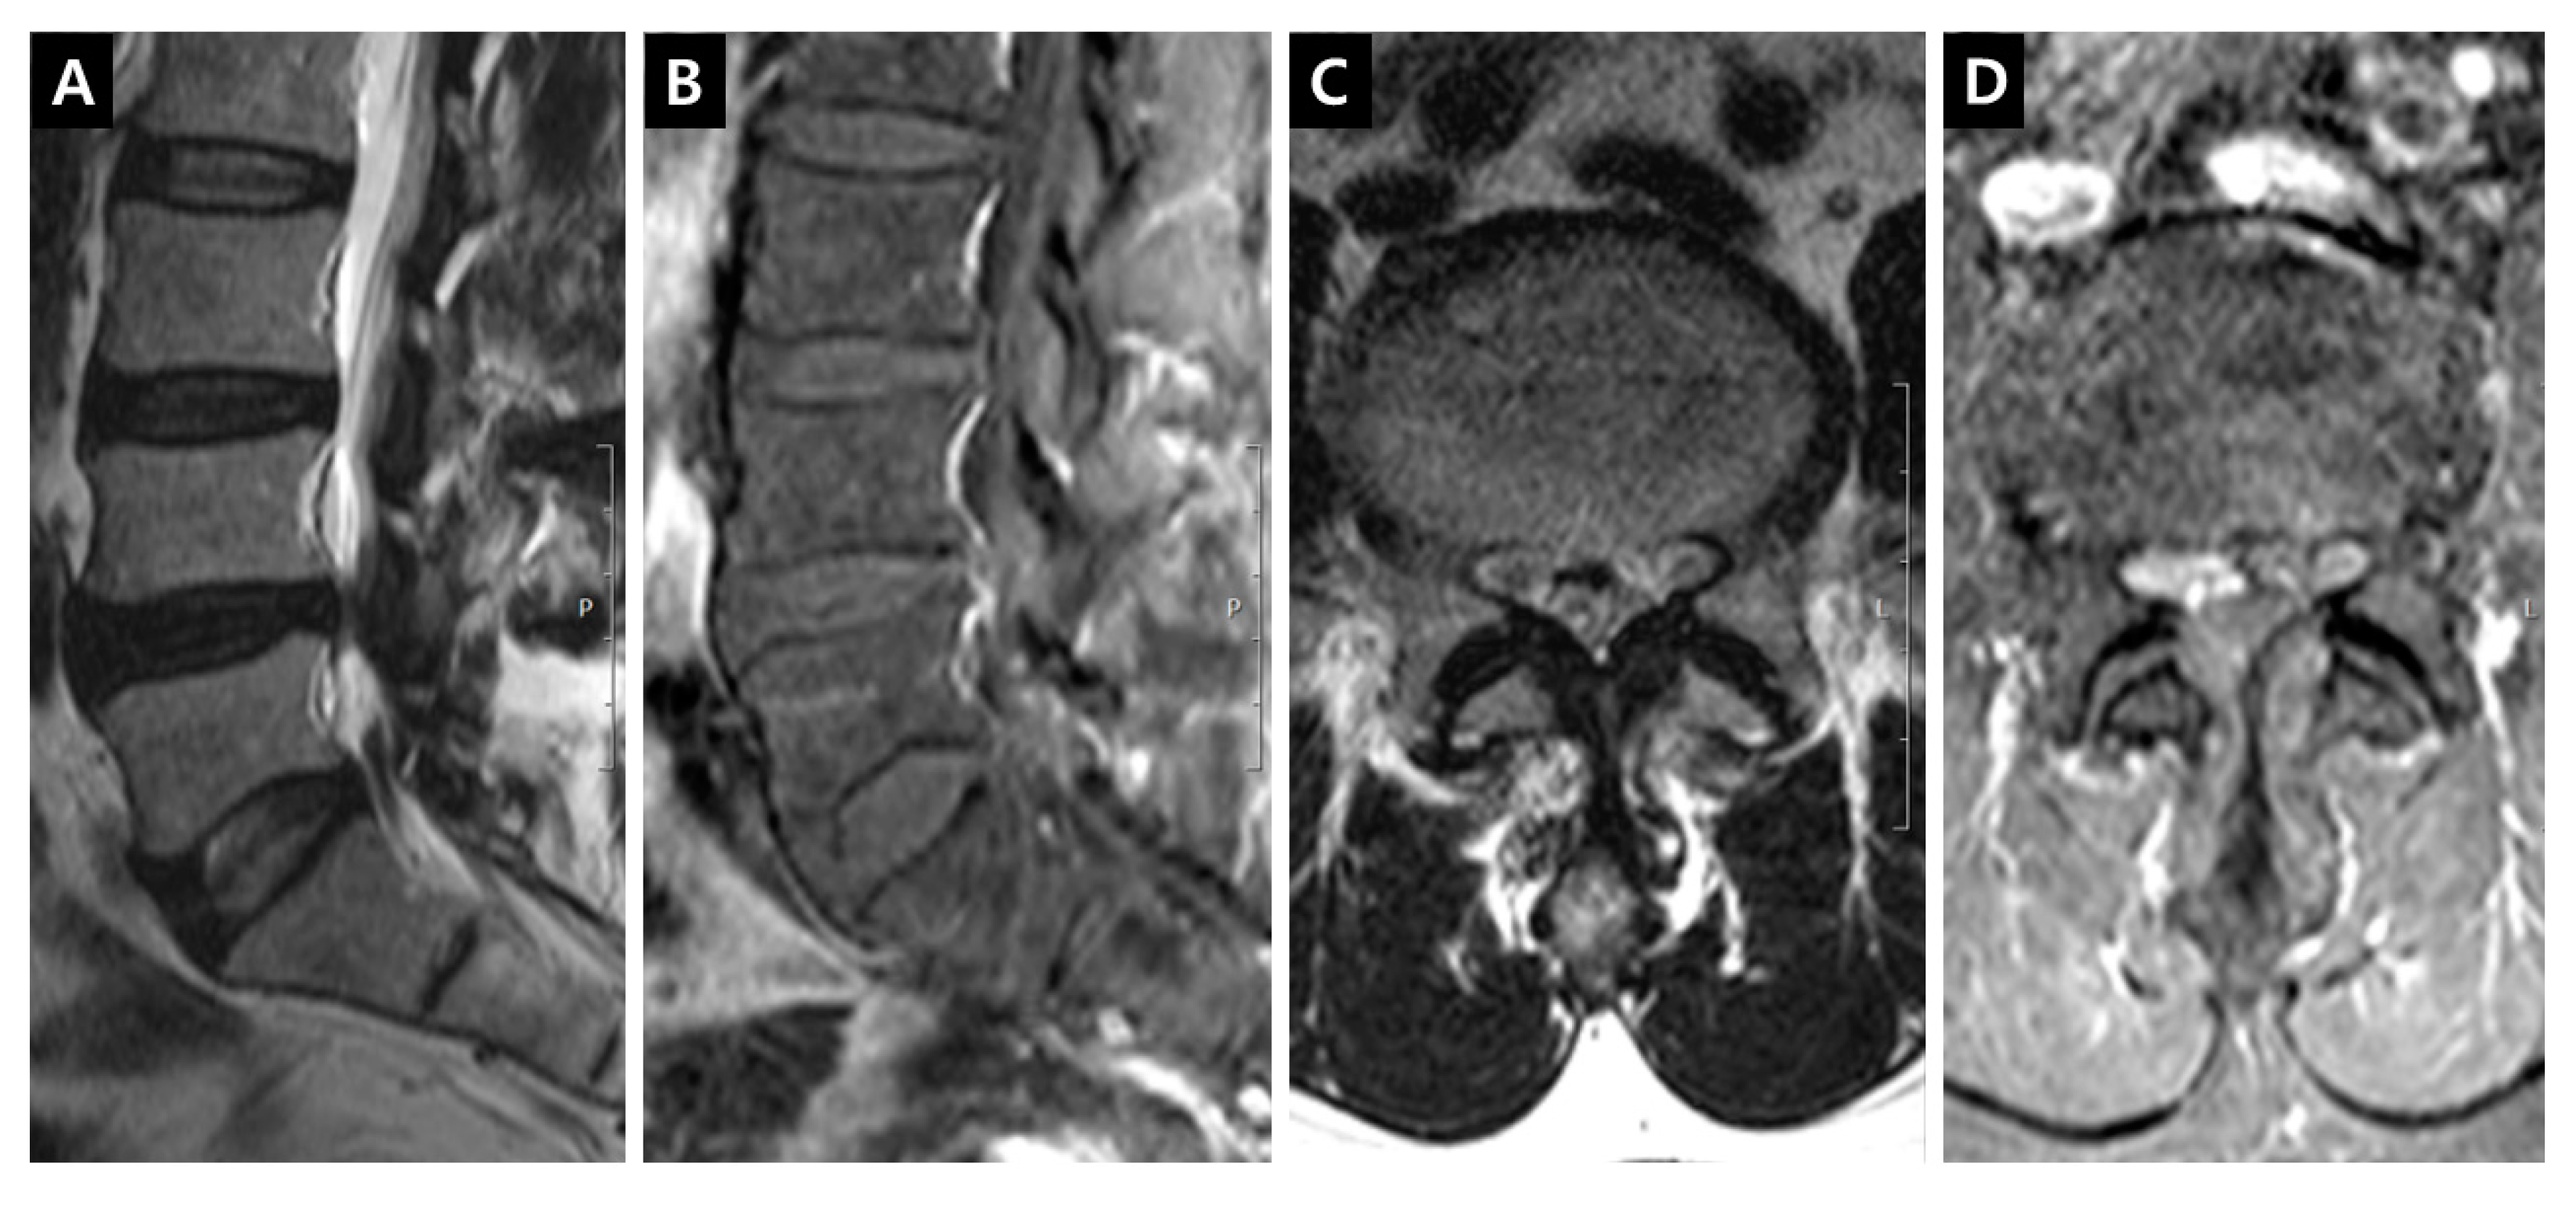

Figure 3. Enhancement patterns: dorsal epidural vein (DVCE). (A) T2-weighted midsagittal image; (B) Fat-suppressed enhanced T1-weighted midsagittal image showing the prominent enhancement on the dorsal dural surface; (C) T2-weighted axial image on the L4-5 disc level; (D) Fat-suppressed enhanced T1-weighted axial image on the L4-5 disc level, the definite enhancement on the ventral surface of ligamentum flavum in the dorsal epidural space can be seen.

DCSAs were measured on the T2-weighted axial plane at the most stenotic level in all stenosis groups and at the L3–4 and L4–5 levels in the control group. The presence of enhancement patterns such as PVCE, DVCE, and IRCE was assessed qualitatively at the level of stenosis. PVCE indicated the enhancement of the periradicular vein and was regarded as a part of the longitudinal vein in anterior IVVP or PEVC (Figure 2). DVCE designated the enhancement of the dorsal epidural venous plexus in the posterior IVVP (Figure 3). IRCE indicated the enhancement of the intraradicular vein within intrathecal rootlets (Figure 4). The author assumed that these enhancement patterns (PVCE, DVCE, IRCE) developed according to the degree of venous congestion and reflux.